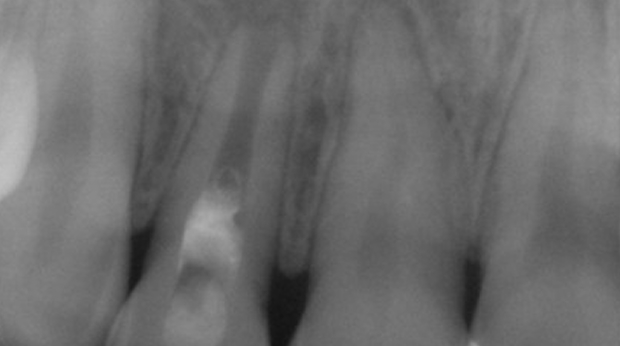

임플란트와 사랑니 발치는 외과적 시술로 잇몸을 절개하는 외과적 시술은

짧으면 짧을 수록 시술 후 붓기와 통증이 최소화됩니다.

치과의사 경력 14년차 구강외과 전문의가 빠르고 안전하게, 아프지 않게 수술해 드립니다.